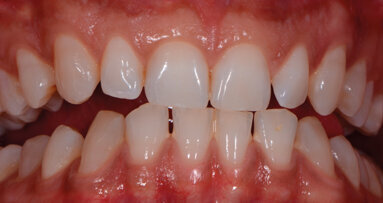

Case report Un paziente di anni 29 di sesso maschile si presenta per un controllo. In apparente salute sistemica, riferisce di avere bisogno di mostrare un sorriso luminoso e bianco poiché, essendo un odontoiatra, ha deciso di dedicarsi alla pratica clinica quasi esclusivamente estetica e cosmestica, comprese le tecniche di antiagening periorali (fotoringiovanimento e filler), e vuole valorizzare nei confronti dei suoi pazienti il suo aspetto curato e il sorriso smagliante, a mo’ di modello per corretti stili di salute orale; essere quindi testimonial esso stesso dell’efficacia delle terapie proposte.